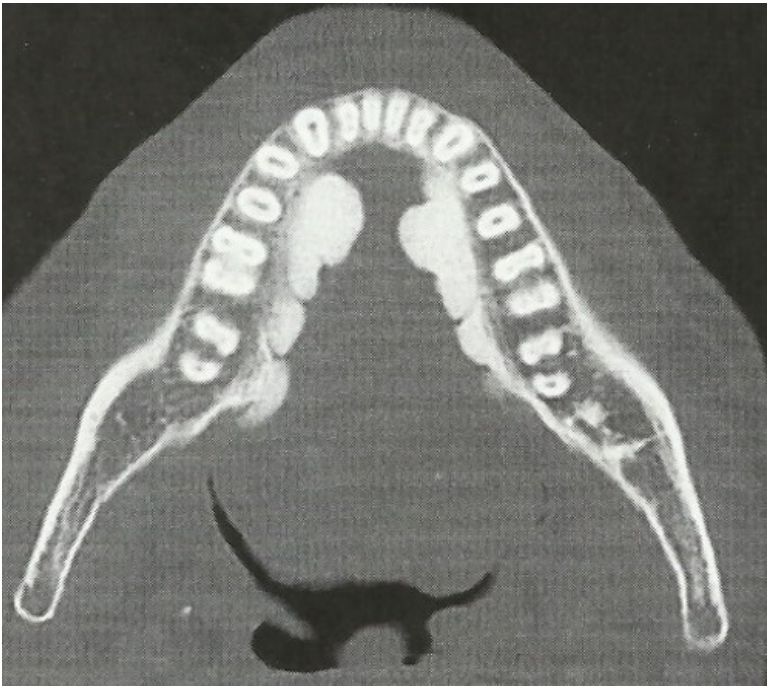

79.圖示影像是以何種方法拍攝? (A)magnetic resonance imaging (B)occlusal radiography (C)panoramic radiography (D)computed tomography